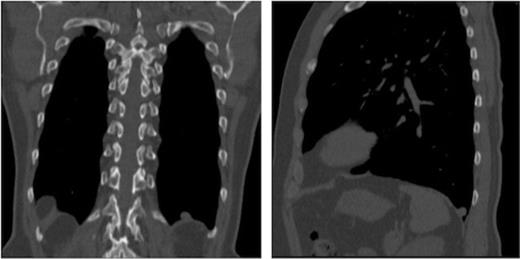

A 71 year old male Caucasian teacher was incidentally found on Computed Tomography (CT) of the colon to have two well-defined nodules in the left hemithorax. There was no other abnormality within the thorax or abdomen. He was a non-smoker, with only minimal exposure to a classroom with an asbestos roof. He had no history of chest trauma, intervention or pleurisy. A further high resolution CT scan of the chest demonstrated a well-defined rounded 11mm nodule arising from the pleura of the left diaphragmatic surface (Figures 1a and b). A larger 15mm rounded soft tissue lesion containing calcification was noted in the pleura of the left paravertebral region adjacent to the lower lobe (Figure 2). No other abnormality was present in the chest. The multidisciplinary decision at that time was to monitor with an interval high resolution CT scan of the thorax. Four months later the scan showed a slight increase in size of both nodules and a decision with the patient and by a multidisciplinary meeting was to resect the nodules for diagnosis. At this stage the nodules were in the same position as on the initial scan.

Coronal CT image of the thorax demonstrating nodule 1 overlying the left hemidiaphragm. Sagittal CT image of the left hemithorax demonstrating nodule 1 overlying the left hemidiaphragm